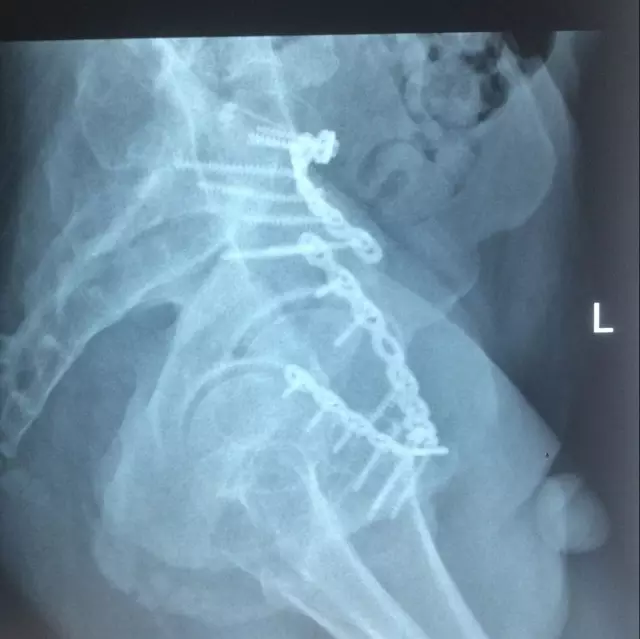

為此,科室在黃東永科主任為首的專(zhuān)科團(tuán)隊(duì)帶領(lǐng)下,經(jīng)過(guò)周密計(jì)劃、分析討論、總結(jié)過(guò)往的經(jīng)驗(yàn),制訂了嚴(yán)密的手術(shù)方案,并得到了南方醫(yī)科大學(xué)附屬第三醫(yī)院曾參軍教授的指導(dǎo),于8月20日在插管全麻下順利為該患者施行了骨盆多發(fā)骨折的手術(shù),術(shù)后效果較好,患者自覺(jué)滿意。

患者術(shù)后復(fù)查X片情況

術(shù)后X片